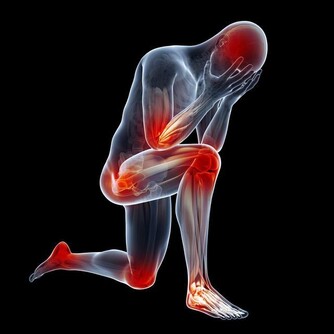

***3、容易抽筋,渾身乏力***

身體抽筋,很多人會默認是缺鈣導致的,但在補充鈣質後仍然反复抽筋,並且還會產生嚴重的疼痛四肢乏力的問題,還應該考慮缺鉀的原因。因為鉀元素能夠在身體內調節平滑肌的收縮,從而改善肌肉運動。但長期缺鉀會導致肌肉收縮異常,導致抽筋,痙攣渾身乏力